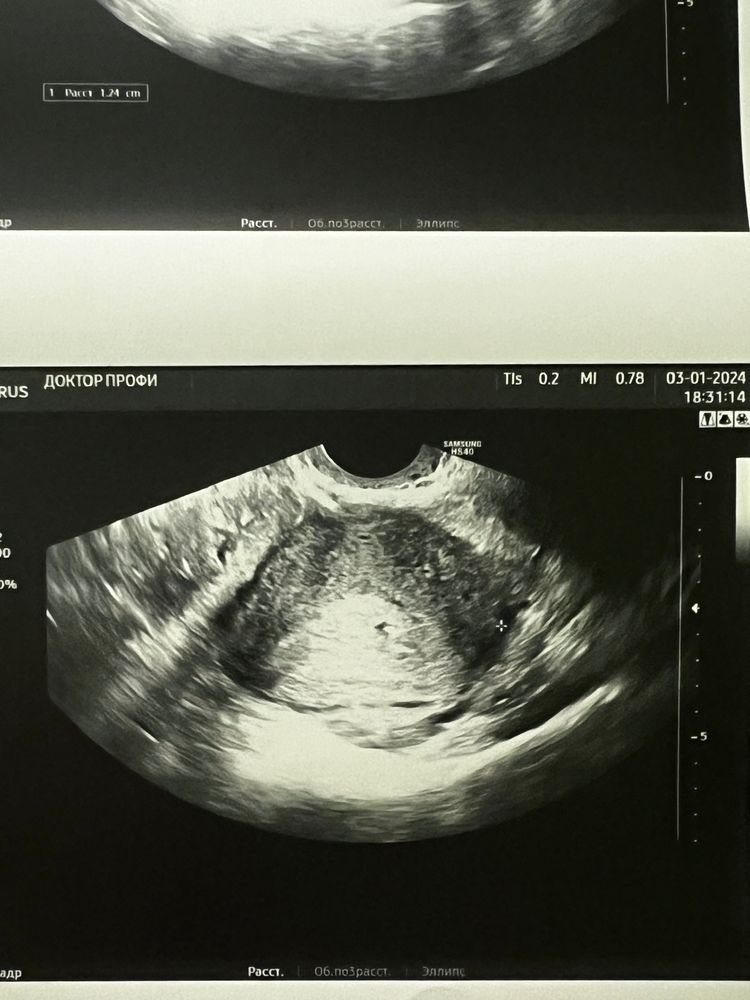

Изображение Череппааашка по имени Натааашка , вот эта точка в матке 🥺

05.01.2024

Полина, по картинке не сказать . Они смотрят кровотоки , и так определяют . Очень вероятно ,что это оно . Но сильно лучше не привязывайтесь к этой беременности 😔 лучше через время еще узи сделайте . Но хгч очень плох ( если не пойдет в рост , то без вариантов (

Изображение Вот так как-то

Изображение Полина,